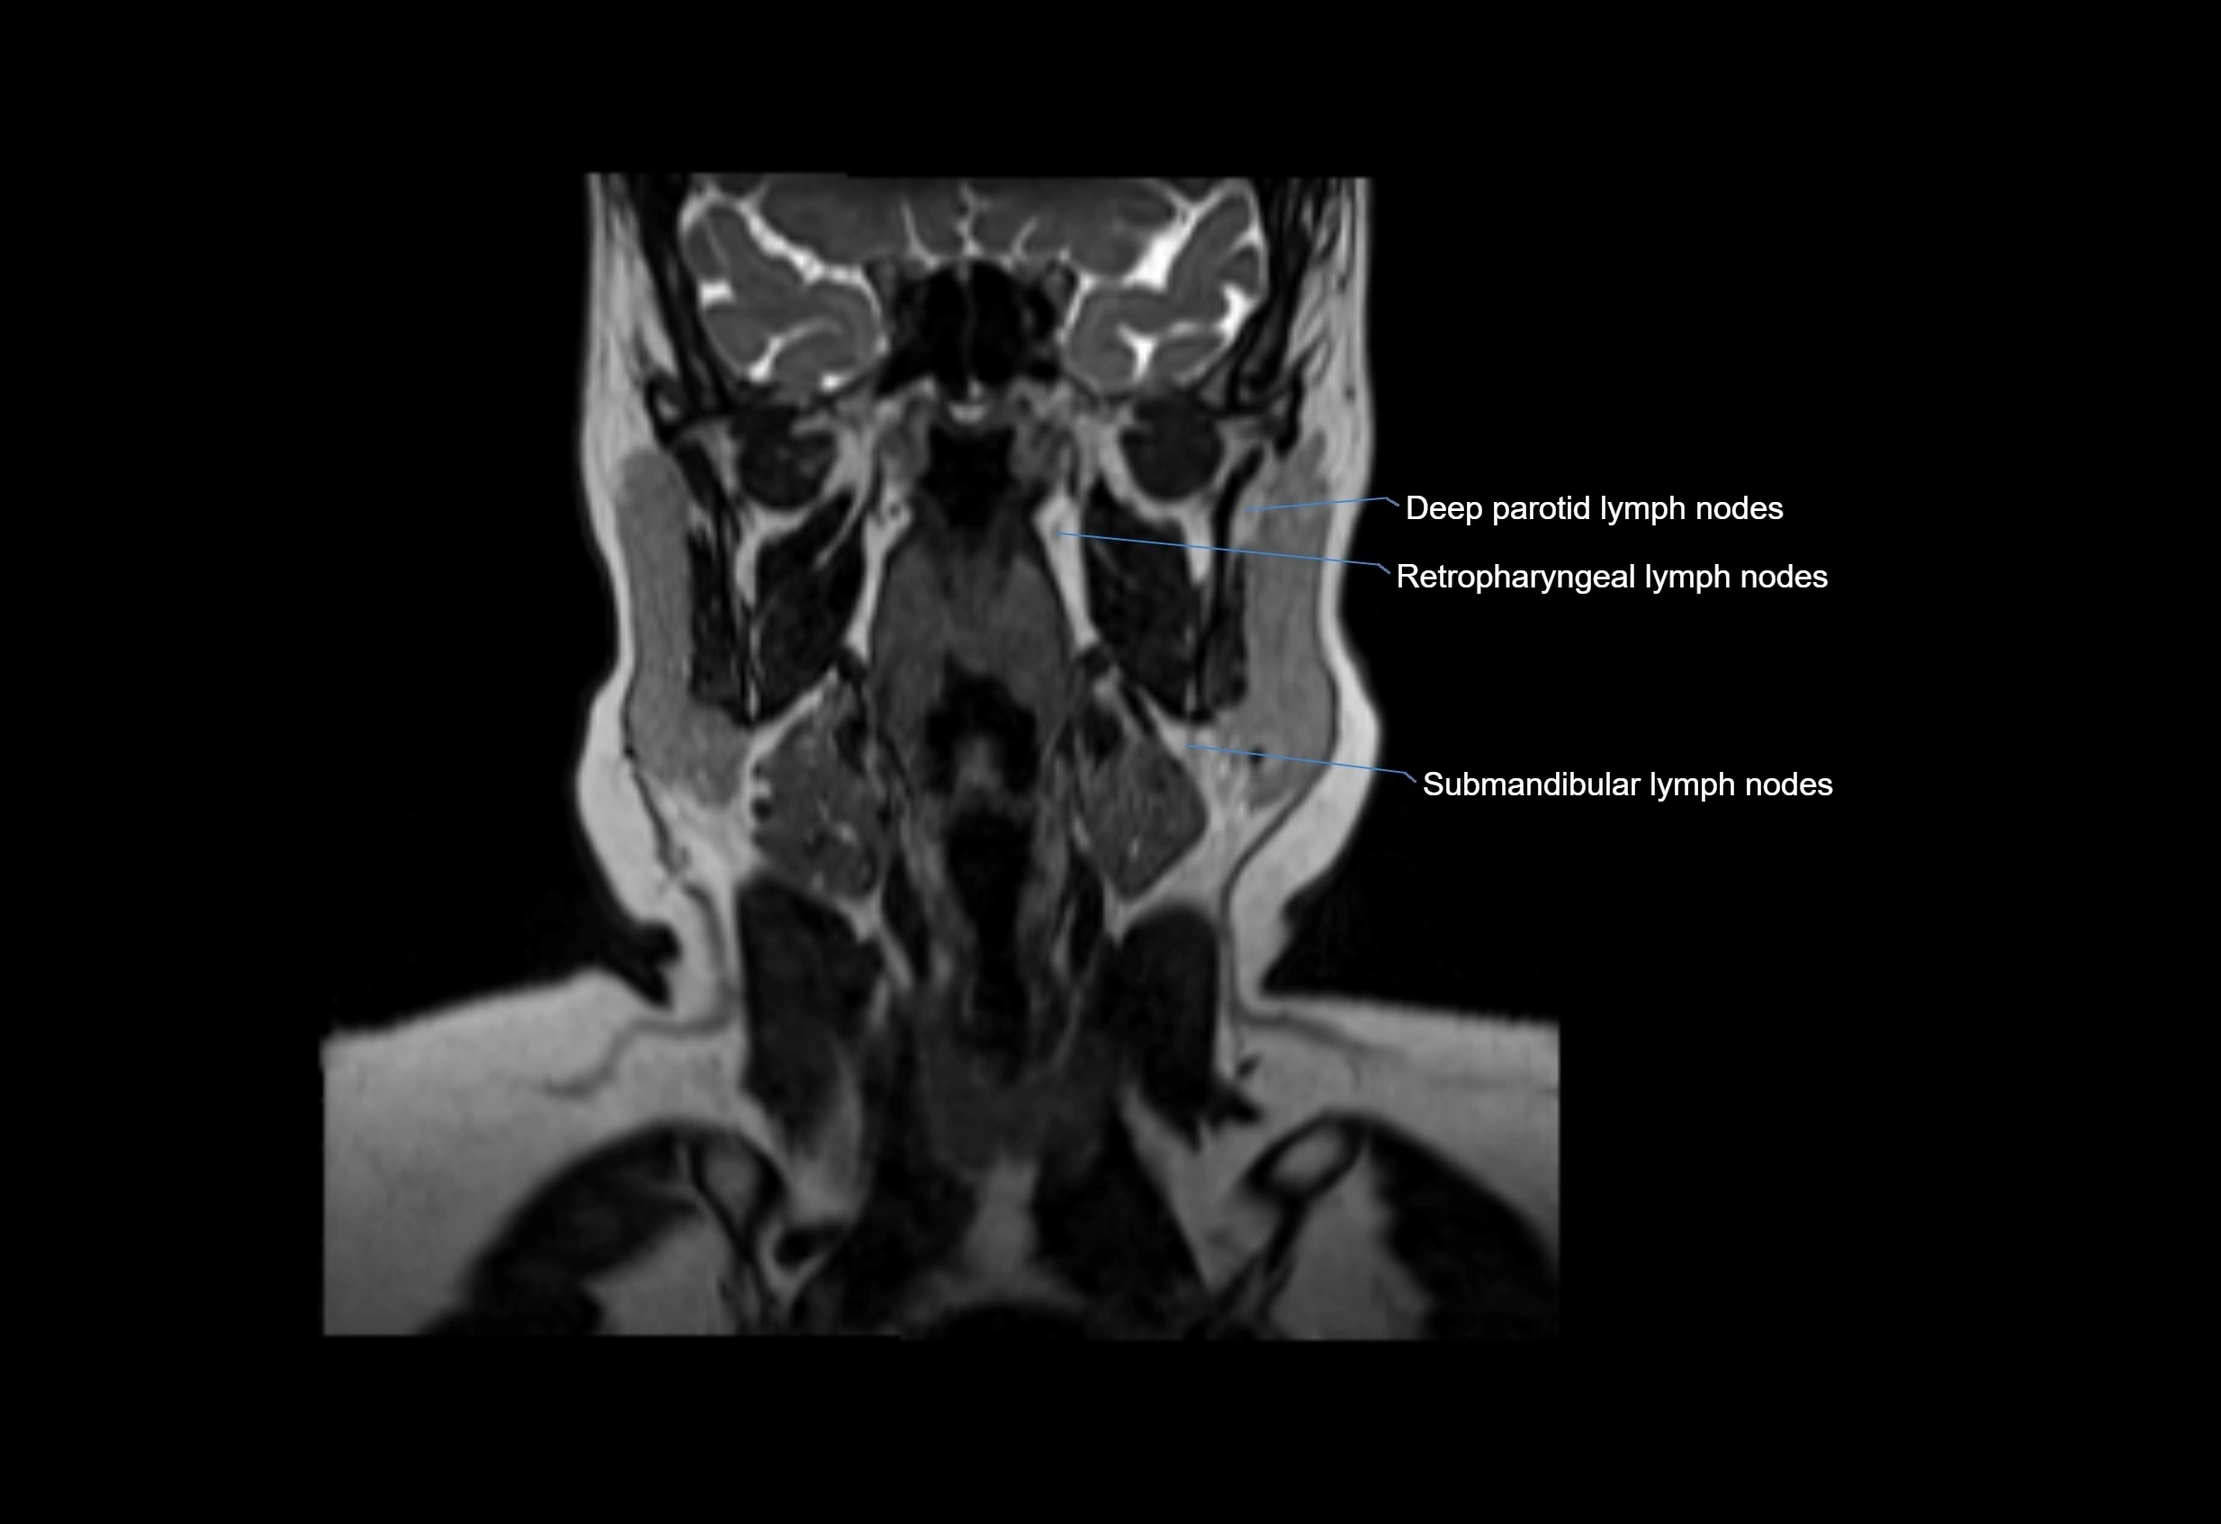

MRI images

image